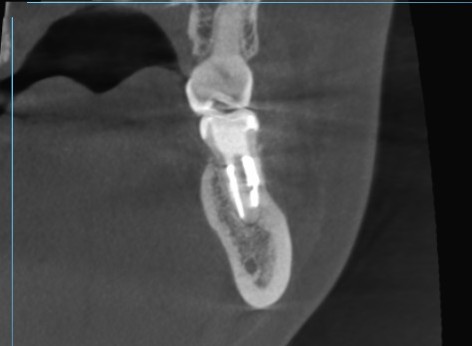

当院で定期検診を行い、5年後のCT撮影で予後を確認しました。

横側から見てみると根の先の黒い影が消えています。

炎症が無くなり骨が再生しています。5年後で再発の兆候は無く安定しています。

最初のCT画像ももう一度見てみましょう。

術前です。根の先と周囲に黒い影がしっかりと見えます。

断面で確認です。

根の先端の黒い影が全くありません。

右の根管は閉鎖していましたが完治しています。

遠心根の断面も見ます。

左側の穿孔していた先の骨も再生し、根の先の黒い影も無くなっています。

5年経過しましたが安定しています。しっかりと治っています。